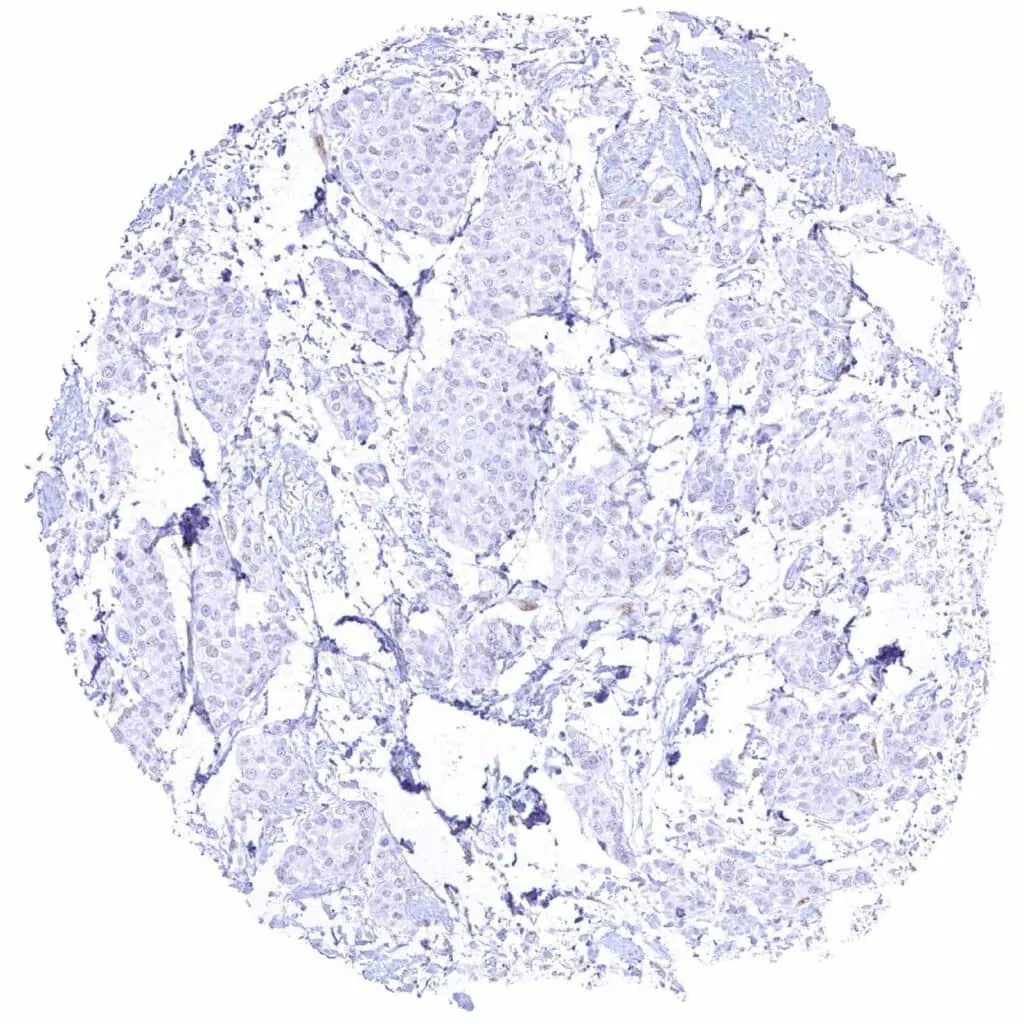

Prostate – Cyclin E1 negative adenocarcinoma (Gleason 3+3=6)